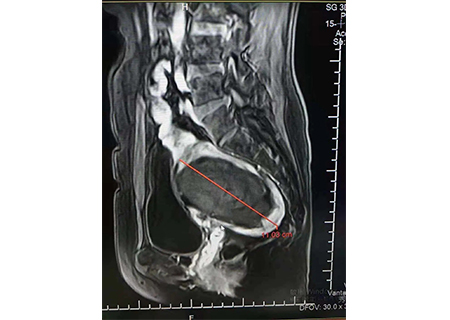

消融坏死后11公分

消融坏死对比图如上↑

治疗后一周追踪,肌瘤已经从14公分降为11公分,患者的盆腔压迫感也减轻很多。